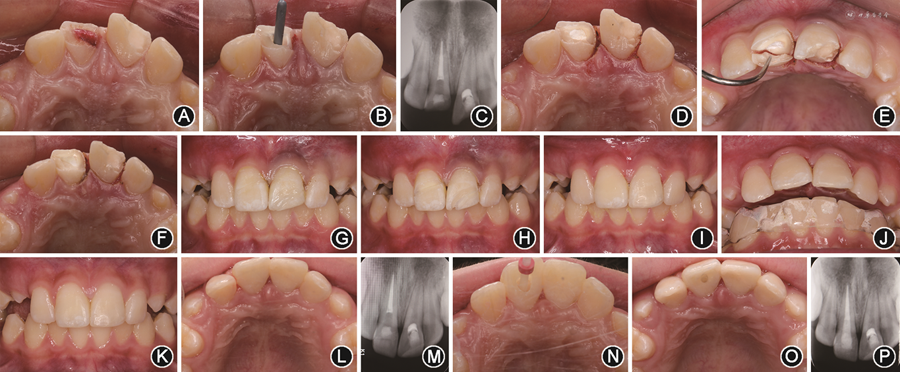

(1)21牙髓切断术:21唇侧使用4%阿替卡因肾上腺素注射液(碧兰公司,法国)行局部浸润麻醉,于露髓处扩大开髓洞型,切除全部冠髓,生理盐水冲洗止血后,采用生物陶瓷材料(iRoot-BP Plus,Innovative Bioceramix Inc,加拿大)盖髓,玻璃离子水门汀(GC,日本)垫底并充填至断面以下约2 mm 处(图2A)。

面像;B:11根管治疗过程;C:11根管治疗术后根尖片示恰填;D:11、21牙龈修整术;E:11腭侧断冠原位粘接过程;F:11腭侧断冠原位粘接后;G:11、21脱落断冠粘接;H:11、21增加唇面固位沟、模糊折裂线;I:11、21完成断冠粘接及树脂修复;J:佩戴下颌

垫后正面

像;K:术后1个月11、21正面

像;L:术后1个月11、21

面像;M:术后1个月11、21根尖片;N:术后1个月11纤维桩修复过程;O:11纤维桩修复后

面像;P:11纤维桩修复后根尖片

面像;P:11纤维桩修复后根尖片(2)11根管治疗术:11唇腭侧使用4%阿替卡因肾上腺素注射液行局部浸润麻醉,于露髓处扩大开髓洞型,可见腭侧折裂线起始于断面以下约1 mm处的髓腔腭侧面,延伸至釉质牙骨质界下方根面;拔髓,根尖定位仪(VDW,德国)测量工作长度为20 mm,使用ProTaper Universal机用镍钛锉(登士柏,瑞士)预备根管至F4,试主牙胶尖到达工作长度(图2B),干燥根管后采用热熔牙胶结合iRoot SP糊剂(Innovative BioCreamix Inc,加拿大)垂直加压充填根管中下段,根尖片示根充恰填(图2C),小干棉球置于根管口,暂封物充填至平齐腭侧折裂线。

(3)11腭侧断冠原位粘接:采用高频电刀(Servotome,法国)修整11近中及腭侧游离龈约1.5 mm,充分暴露断面并形成龈上边缘(图2D);腭侧断冠折裂面清洁干燥后,37%磷酸(Eco-Etch,Ivoclar Vivadent,瑞士)酸蚀折裂面中上段15 s,充分冲洗干燥,酸蚀面涂布薄层通用型粘接剂(Single Bond Universal Adhesive,3M,美国),采用流动树脂(Z350XT,3M,美国)对位粘接断冠,轻柔清除龈沟内溢出的多余粘接剂及树脂,光照固化(图2E,F)。

(4)11、21断冠粘接:高频电刀修整21远中游离龈约1 mm形成龈上断面(图2D);11、21断面及断冠去除薄壁弱尖,断冠髓腔内制备固位沟槽,清洁干燥后37%磷酸各酸蚀15 s,冲洗干燥后涂布通用型粘接剂,采用流动树脂对位粘接各自断冠(图2G),光照固化前清除溢出的多余树脂;为增强断冠粘接的可靠性及改善美观,于11、21唇面折裂线两侧制备短斜面,形成V形凹槽(图2H),采用全酸蚀粘接的方式联合使用流动树脂垫底、复合树脂分层充填,恢复唇面形态(图2I)。

(5)制作并佩戴下颌

垫:制取下颌牙列藻酸盐印模并灌注超硬石膏模型,制作1.5 mm厚质硬压膜

垫,并磨开32—42区切端,佩戴后11、21与对颌牙无咬合接触(图2J),进食及有夜磨牙症状时必须佩戴,降低对11、21的不良

力,佩戴2周。

(6)1个月后复诊:11、21无不适症状,断冠粘接及充填物完好(图2K),无叩痛,腭侧牙龈恢复良好、色泽正常(图2L),根尖片示11、21根尖周无异常暗影(图2M)。按计划11行纤维桩加固:腭面开髓,去净暂封,预备钻(2号,3M ESPE,美国)预备桩道至根尖段保留5 mm牙胶封闭,试纤维桩(2号,3M ESPE,美国)(图2N),桩道清洁干燥后采用小蜜蜂胶囊(RelyXTM Unicem,3M ESPE,美国)粘接纤维桩,调

(图2O,P)。